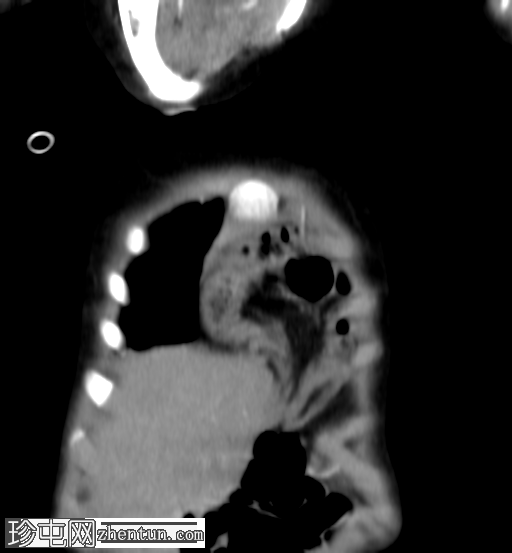

矢状位增强扫描

动脉期

横结肠及其系膜经膈前部缺损疝入前纵隔。

未见肠管扩张或梗阻。

双肺实变影,提示呼吸道感染。